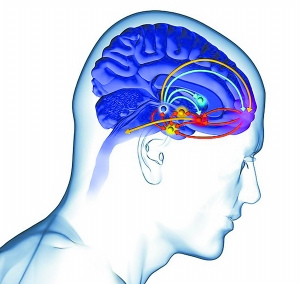

美国印第安纳大学研究人员发现,啤酒的特殊口味可引发大脑中多巴胺的生成。具有酗酒家族史的人们具有更高的多巴胺指数,多巴胺是与大脑回报和愉悦中心区域相关的一种神经递质。

这项研究扫描了饮用啤酒和运动饮料佳得乐的49位男性测试者,结果表明饮用啤酒者比饮用佳得乐具有更显著的多巴胺活跃性,同时,测试者在饮用少量啤酒之后表示更渴望饮用啤酒,但这种效应不会出现于运动饮料,虽然运动饮料的口感更佳。

每位男性测试者每15分钟饮用15毫升啤酒,因此他们不会感觉到酒精作用。英国苏塞克斯大学实验心理学教授戴-斯蒂芬斯教授指出,这项研究首次令人信服地证实了啤酒口味可在大脑产生特殊刺激效果。